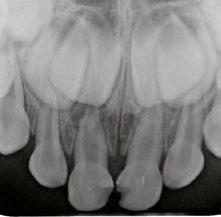

Several clinical solutions exist for primary anterior teeth with multisurface decay. Full coronal restoration of carious primary incisors may be indicated when caries is present on multiple surfaces, pulpal therapy is indicated, caries may be minor, but oral hygiene is very poor, or in a child with severe early childhood caries or a high caries risk diagnosis.1 Depending on the clinical scenario, a minimally invasive approach with the utilization of a high viscosity glass ionomer cement (HVGIC), with or without the combination of silver diamine fluoride (SDF) in a strip crown form, may pause the caries progression and provide an adequate clinical solution. Resin composite strip crowns have shown 80% retention rates and adequate parental satisfaction,1-4 although composite resin strip crowns have shown lower retention rates in teeth with decay involving three or more surfaces and particularly in children with a high caries risk4-6 (Figure 1). This could be from the continued high caries risk behaviors of the patient, as composite resin strip crowns in this population have shown to have increased inflamed marginal gingiva and gingival bleeding, increased plaque retention along the restoration, and loss of some restorative material.5,6

2: NuSmile® Anterior Zirconia crowns at 2-year follow up. Note the high amount of plaque accumulations along the untreated cuspid and existing stainless-steel crowns

A 2-year-old male who received full mouth dental rehabilitation (FMDR) under general anesthesia presented for his 6-month recall at 2-year post FMDR. He had significant plaque accumulations with poor oral hygiene along his existing stainless-steel crowns (SSCs) and non-treated teeth. Additionally, the patient had gingival bleeding and gingival inflammation

Figure 1: Occlusal films at recall visit in high caries risk patients showing loss of material and recurrent decay in composite resin strip crowns Figure

around these clinical sites. His anterior zirconia crowns showed healthy gingival margins with little-to-no plaque accumulations. This positive clinical finding is from the highly polished nature and biocompatibility of pediatric zirconia crowns. These restoration features limit plaque accumulations on the restoration and along the marginal gingiva, providing a localized positive aspect directly related to the choice of restorative material (Figure 2).